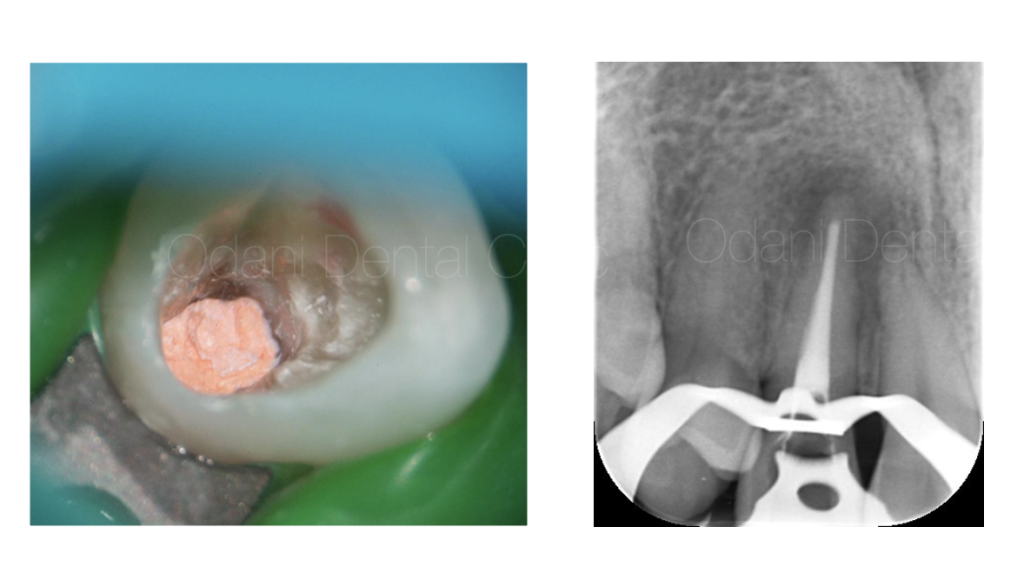

まず、ラバーダム防湿を行い、唾液の侵入のない環境づくりを行った上で、周囲をよく消毒してから、30倍まで拡大できるマイクロスコープ下で、根管内に詰まっていた詰め物や汚れを除去後に清掃・洗浄を丁寧に行いました。洗浄には、薬剤や超音波洗浄に加え、超弾性ニッケルチタンファイルやEr:YAGレーザーも併用し、根管内の細菌除去を徹底し、根管充填(根の中の詰め物)を行いました。

根管充填時の状態です。